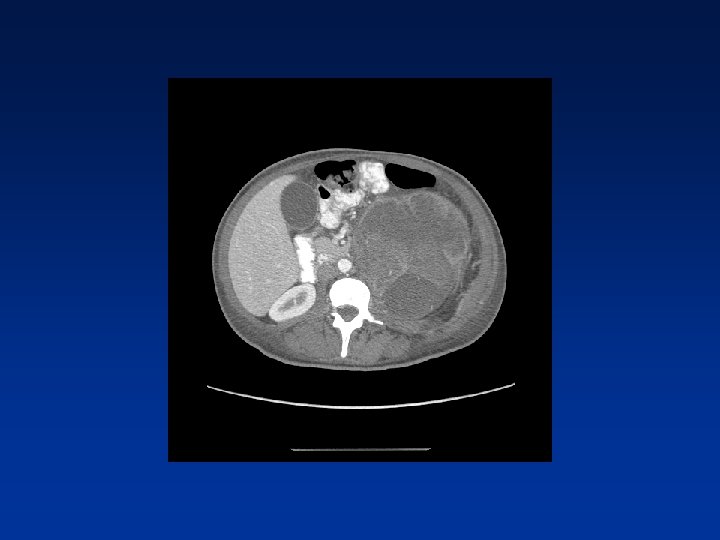

CASE